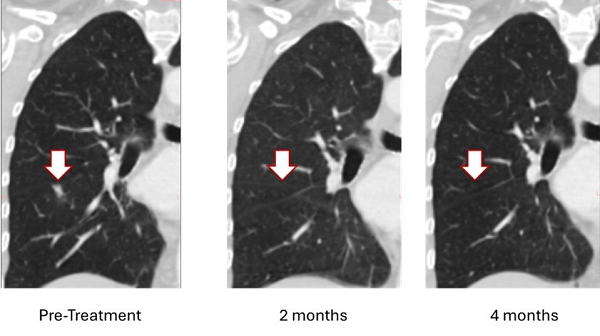

On February 3, 2025, the Company announced an unprecedented clinical response including resolution of a lung metastasis (breast cancer tumor that spread to the lung) with stable disease elsewhere, The patient is the first metastatic breast cancer (MBC) patient treated with Bria-OTS™. Bria-OTS™ is a personalized off-the-shelf immunotherapy, currently under investigation in a Phase 1/2a dose escalation study (ClinicalTrials.gov identifier: NCT06471673) in metastatic recurrent breast cancer. Bria-OTS™ represents a personalized, next generation, advancement of BriaCell’s lead candidate Bria-IMT™ which is currently in a pivotal Phase 3 study for metastatic breast cancer.

On April 24, 2025, BriaCell Confirmed 100% Resolution of Lung Metastasis with Bria-OTS (Figure 1). Complete resolution of lung metastasis confirmed at 4 months follow-up in a hormone receptor positive (HR+) breast cancer patient. Treatment well-tolerated and the patient remained on study with stable disease elsewhere. Sustained clinical response supports Bria-OTS personalized, off-the-shelf immunotherapy approach in Phase 1/2a metastatic breast cancer study.Figure 1: Treatment with Bria-OTS monotherapy resulted in 100% resolution of tumor in the lung of the MBC patient following 2 months of therapy and confirmed at 4 months of therapy1 (axial and coronal views)

1 Note that the other white dots in the lungs are blood vessels.

As shown, the lesion in the patient’s right lung is undetectable after two months and confirmed resolved at 4 months. The updated images supersede those previously reported.